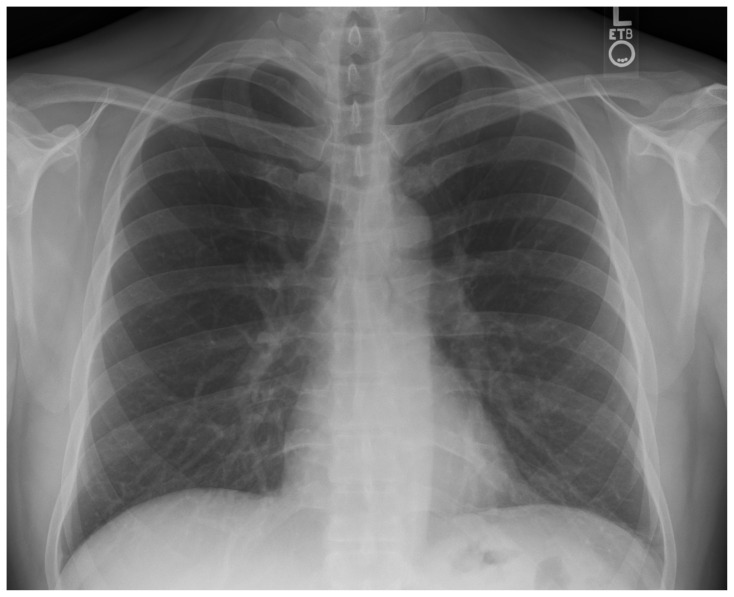

| #6 | CXR |

- List appropriate laboratory and imaging studies to include complete blood count (CBC), complete metabolic panel (CMP), magnesium level, and computed tomography (CT) scan of the brain.